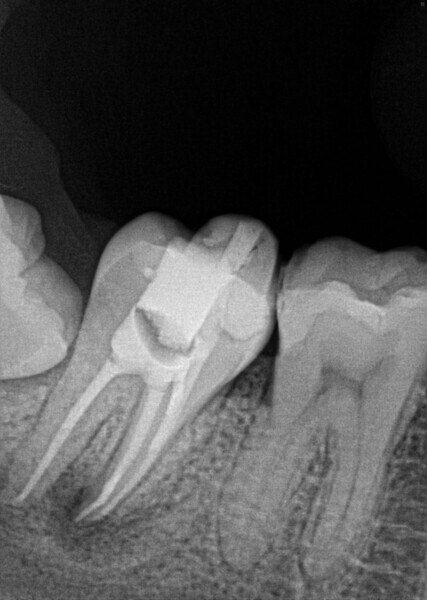

Fig. 16a: Case treated with a Bioceramic master cone, sealer and putty. Note the excellent apical control in this blunderbuss apex. (Courtesy of Dr. Rico Short)

Fig. 16b: Case treated with a Bioceramic master cone, sealer and putty. Note the excellent apical control in this blunderbuss apex. (Courtesy of Dr. Rico Short)